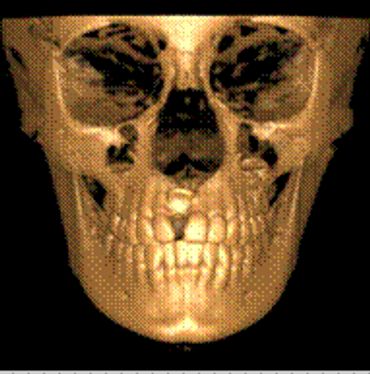

CBCT is a digital x-ray scanner specifically designed for scanning the head and jaws. The scanner rotates 360 degrees around the patient's head in a matter of seconds. The x-ray is a low energy fixed anode tube similarly used in panoramic machines. This method reduces radiation scatter common to most conventional x-rays. The cone shaped x-ray provides 360 views that can be presented in 2D image and 3D volume for advanced planning and diagnostic support.

This one scan provides more images than plain film conventional imaging, with complete visualization of the patient's entire maxillofacial region. These images clearly display TM disorders, impacted teeth, critical bone and tooth relationships, oral- nasal airways, para-nasal sinus, mandibular canal and difficult to see pathologies within one volume. The user friendly software system reconstructs true size, distortion free, high resolution images.

The CBCT scanner is fast, comfortable (nothing goes in the mouth), and painless for patients. It provides a complete set of maxillofacial images with less radiation than conventional orthodontic and medical type CT work-ups. CBCT now can re-create true size cephalometric and panoramic images, virtually eliminating the need for conventional orthodontic x-rays, so your patients will be comforted by the knowledge that you have all the information needed to evaluate and plan their treatment